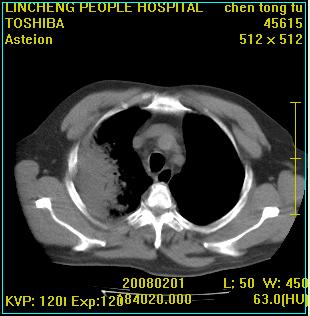

患者,男性,62岁。主因头晕,发热,咳嗽6天,高热达39度,esr19mm/h,wbc 3.9×10 9/l

大叶性肺炎并胸膜炎

右肺大叶性肺炎,胸腔积液。建议痰检。

实变区见空气支气管征,支气管通畅,考虑为大叶性肺炎,右侧少量胸水

1)考虑为:右肺感染性病变。建议:抗炎治疗复查。2)右侧少量胸腔积液。

考虑为右肺大叶性肺炎,胸腔积液,建议必要时纤维支气管镜检查,以排除肿瘤性病变。

右肺炎症并右侧胸腔少量积液。

大叶性肺炎并胸膜炎、胸水。

考虑为右肺大叶性肺炎伴少量胸腔积液,建议复查,如病变不吸收或吸收不明显,建议纤维支气管镜检查,除外细支气管肺泡癌的可能。

右侧大叶性肺炎,右侧少量胸腔积液.

实变区见空气支气管征,支气管通畅,考虑为大叶性肺炎,右侧少量胸水。